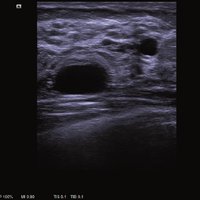

Das ACUSON NX2 Ultraschallsystem besitzt eine zukunftsfähige digitale Plattform mit nahezu unerreichter Bildqualität und sorgt für effiziente und zuverlässige Diagnosedaten. Die Vielseitigkeit des Ultraschallsystems wird mit einem großen kompatiblen Portfolio an Schallköpfen gedeckt, und so ist für jeden Anwendungsbereich etwas dabei. Die Bedienkonsole ist intuitiv aufgebaut und optimiert und erlaubt bis zu vier nach vorne gerichteten Schallkopfanschlüssen für eine enorme Effizienz und schnellen Workflow. So lassen sich bei der fetalen Bildgebung außergewöhnlich detailgetreue Darstellungen des Fetus im Gesicht zeigen oder durch die herausragende Farbdopplersensitivität bei der Darstellung der kleinen Gefäße des zystischen Schilddrüsenknotens kleinste Details erkennen. Weiterhin besticht das NX2 mit einfacher Aufrüstbarkeit bei wachsenden Anforderungen für Ihre zukünftigen Anwendungen und kompatible skalierbare Schallköpfe verringern ihren Kapitaleinsatz um bis zu 31 %.